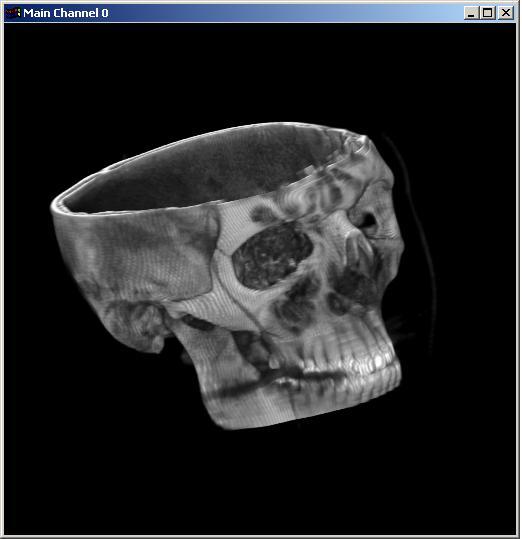

Visible human female CT data

Data

Resolution : 256x256x128

|

Visible human male CT data

Data

Resolution : 256x256x128

|

Visible human male CT data

Data

Resolution : 256x256x128

|

The following 12

images was generated by PC which has NVIDIA's GeForce3 GPU graphics card. The

hardware accelerated rendering techniques are used to make the following images.

To use the GeForce3 hardware, we have to use the OpenGL extensions like

GL_NV_texture_shader2, GL_NV_register_combiners, GL_EXT_texture3D,

GL_EXT_paletted_texture, GL_ARB_multitexture and so on. Since the GeForce3 card

allows the 3D texture shading, the image quality is better than the pixel of

frame buffer based shading in showing two materials at the same time.